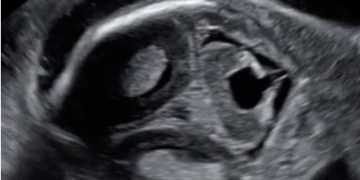

Casi del Mese di Marzo 2023

Cari soci, finalmente online le soluzioni dei casi per il mese di Marzo!!! Grazie a Ilaria Fantasia e Gabriele Saccone!! Caso 1 [pdf-embedder url="https://www.sieog.it/wp-content/uploads/2023/03/caso-clinico-Fantasia-risposta-marzo-2023.pdf" title="caso...